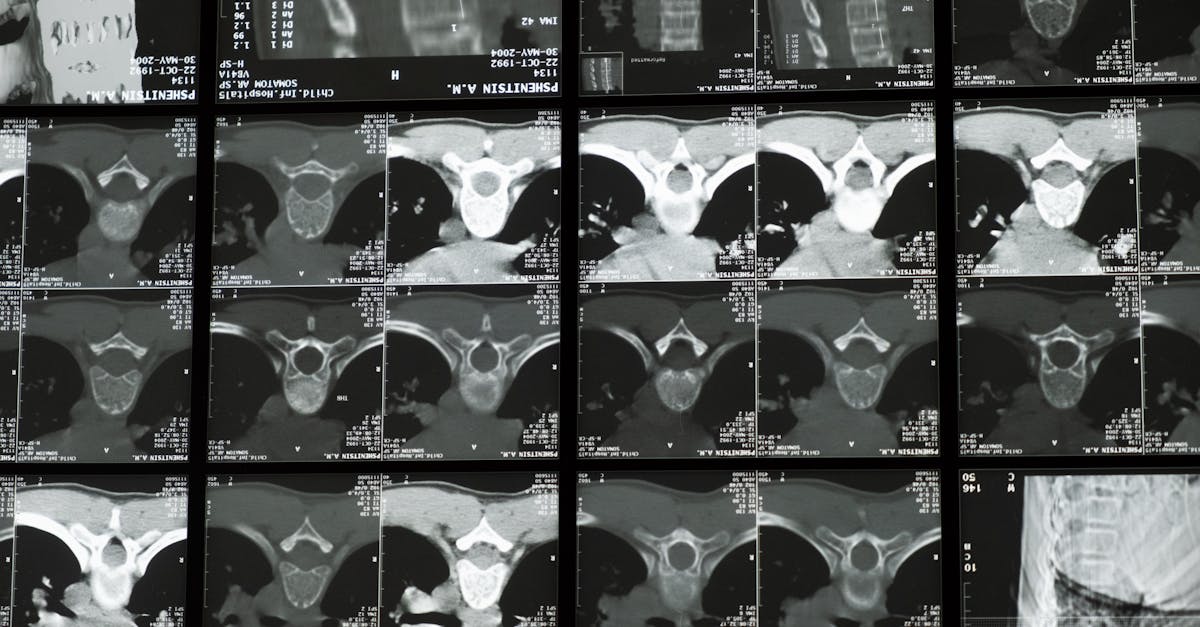

Imagerie médicale

Le diagnostic est souvent confirmé par des techniques d’imagerie médicale telles que les rayons X ou l’IRM. Ces examens révèlent des anomalies anatomiques dans la colonne vertébrale, comme le rétrécissement du canal rachidien. Ils permettent d’observer non seulement l’alignement de la colonne vertébrale, mais aussi l’état des disques intervertébraux et des articulations.

Pour confirmer le diagnostic, des techniques d’imagerie telles que les radiographies, l’imagerie par résonance magnétique (IRM) ou les tomodensitométries peuvent être requises. Ces examens permettent de visualiser les structures osseuses et les tissus environnants, aidant ainsi à détecter des anomalies telles que des hernies discales ou un rétrécissement du canal spinal. L’IRM est souvent privilégiée car elle fournit une vue détaillée des nerfs et des tissus mous, essentielle pour un diagnostic précis.

En cas de suspicion de sténose spinale, le clinicien peut recommander des examens d’imagerie. Les techniques comme les rayons X et l’imagerie par résonance magnétique (IRM) sont fréquemment utilisées pour visualiser la colonne vertébrale et détecter les zones de rétrécissement. Ces examens offrent une image précise des structures osseuses ainsi que des tissus mous, permettant ainsi de confirmer la présence de la sténose et d’évaluer sa gravité.

Deuxièmement, des examens d’imagerie seront souvent sollicités pour visualiser la colonne vertébrale et détecter la localisation précise de la sténose. Ces outils diagnotiques permettent d’évaluer si la moelle épinière ou un nerf est comprimé, ce qui est une information cruciale pour le traitement. Des études radiologiques comme l’IRM sont souvent privilégiées pour leur capacité à offrir des images détaillées des structures internes.